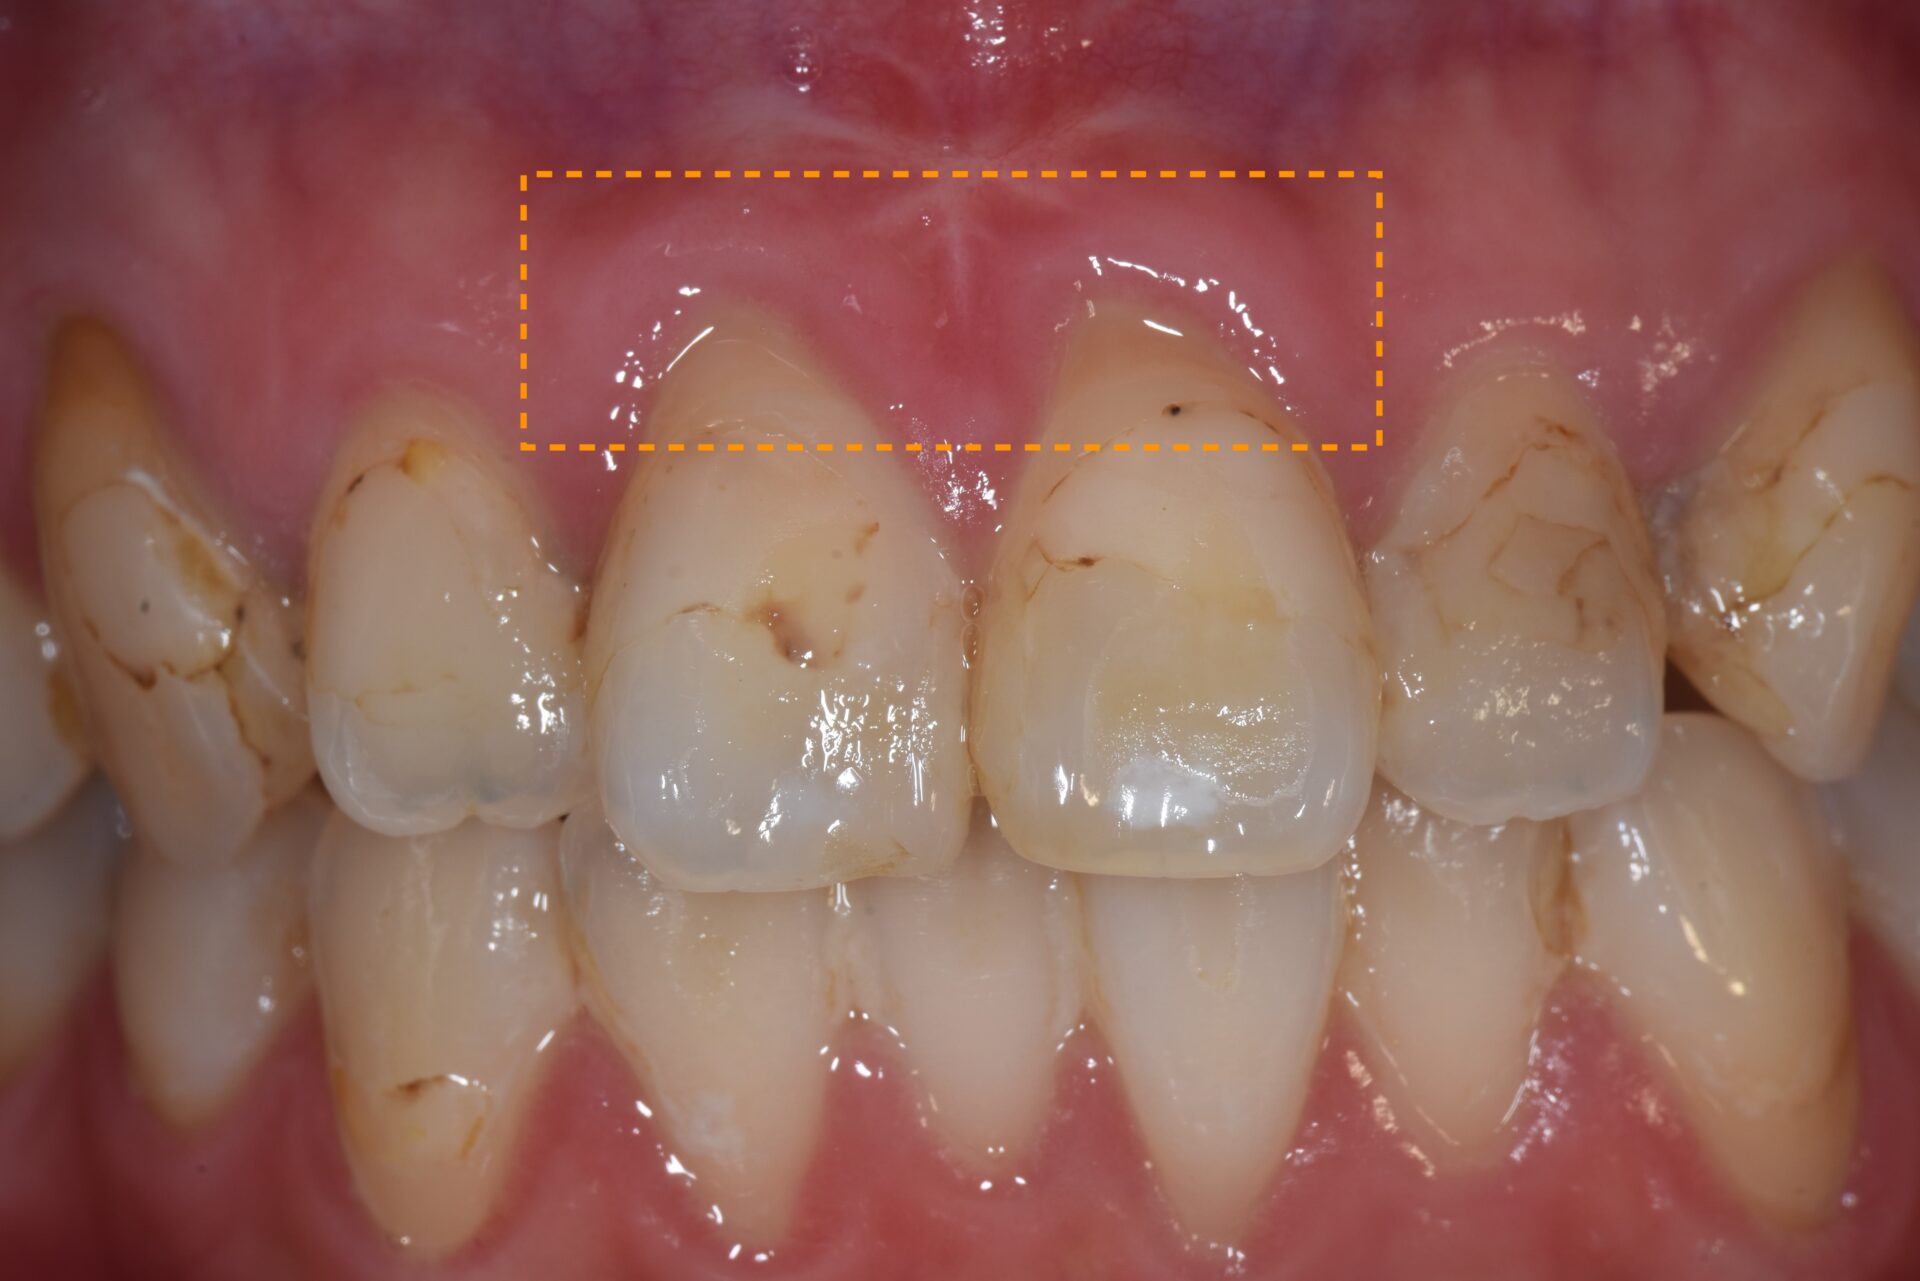

CTG(結合組織移植術) 臨床例②

矯正治療後、下顎前歯部の歯肉が退縮して歯根が露出し、見た目と機能の両面でお悩みでした。歯肉は非常に薄く、付着歯肉も不足しており、ブラッシング時に傷つきやすく、清掃が困難な状態でした。そのため、炎症を繰り返しており、審美的にも不均衡が見られました。長期的に歯周組織を安定させるには、外科的な介入が必要と判断しました。

3か月後には付着歯肉の幅がしっかりと増加し、炎症が改善。歯肉の厚みと付着歯肉の幅が増加し、ブラッシング時の出血や痛みが改善され、審美的に自然で調和の取れた歯肉ラインを獲得。長期的に安定した歯周組織環境を確立することができた。

術前1ヶ月